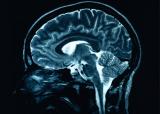

Medical Express рассказывает об уникальной системе - портативном сканере головного мозга. Известно, что стандартные МРТ-сканеры дороги, требуют специальной инфраструктуры и немобильны...